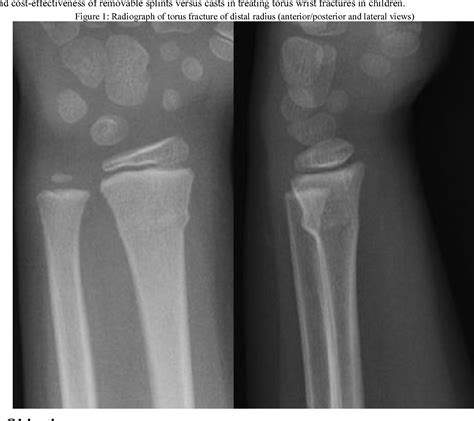

When you bring your child to the emergency room or urgent care, a doctor will perform a physical examination to check for tenderness and range of motion. To definitively diagnose a buckle fracture wrist, the medical team will request an X-ray. Even though the break is small, an X-ray is necessary to confirm that the bone is truly a buckle fracture and not a more severe type that requires specialized attention.